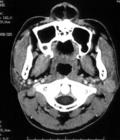

左腮腺淺葉混合瘤:CT平掃示腫瘤呈圓形,邊界清楚,密度高於正常腮腺組織,8例CTS中,5例良性腫瘤呈圓形、界清的充盈缺損,導管受壓變形或移位;3例惡性腫瘤則呈分葉狀、邊界不清的充盈缺損,部分導管中斷,遠端不充盈。全部CTS均作三維重建,圖像逼真,顯示腮腺導管外形、長短和粗細更清楚,顯示腫瘤形態及與周圍組織的關係更直觀。經臨床醫生套用,認為可提高對CTS和常規CT圖像上病變及相關解剖的認識,幫助術前治療方案及預防措施的制定,從而提高手術效果。